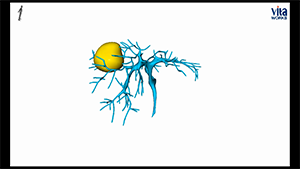

腹腔镜原位解剖性右半肝切除术治疗初始不可切除肝癌

作者:陶海粟 | 作者单位:南方医科大学珠江医院